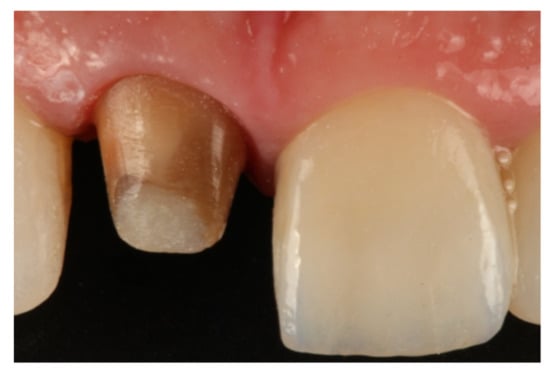

- Agustín-Panadero, R.; Solá-Ruíz, M.F. Vertical preparation for fixed prosthesis rehabilitation in the anterior sector. J. Prosthet. Dent. 2015, 114, 474–478. [Google Scholar] [CrossRef] [PubMed]

- Agustín-Panadero, R.; Serra-Pastor, B.; Fons-Font, A.; Solá-Ruíz, M.F. Prospective Clinical Study of Zirconia Full-coverage Restorations on Teeth Prepared with Biologically Oriented Preparation Technique on Gingival Health: Results After Two-year Follow-up. Oper. Dent. 2018, 43, 482–487. [Google Scholar] [CrossRef] [PubMed]